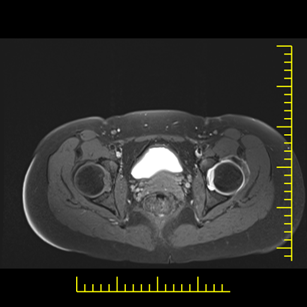

22. veljače 2026.Artrografija zglobova je specijalizirana dijagnostička metoda kojom se uz primjenu kontrastnog sredstva detaljno prikazuju strukture unutar zgloba – hrskavica, labrum, ligamenti, kapsula i tetive.

Artrografija kuka

MR artrografija kuka posebno je važna kod sumnje na oštećenje acetabularnog labruma i femoroacetabularni impingement (FAI).

Prednosti u odnosu na standardni MR

- bolja vizualizacija labruma

- jasnije definirane pukotine hrskavice

- preciznija procjena intraartikularnih lezija

Kod mlađih pacijenata s bolovima u kuku artrografija može otkriti rane promjene koje još nisu vidljive na klasičnoj magnetskoj rezonanciji.